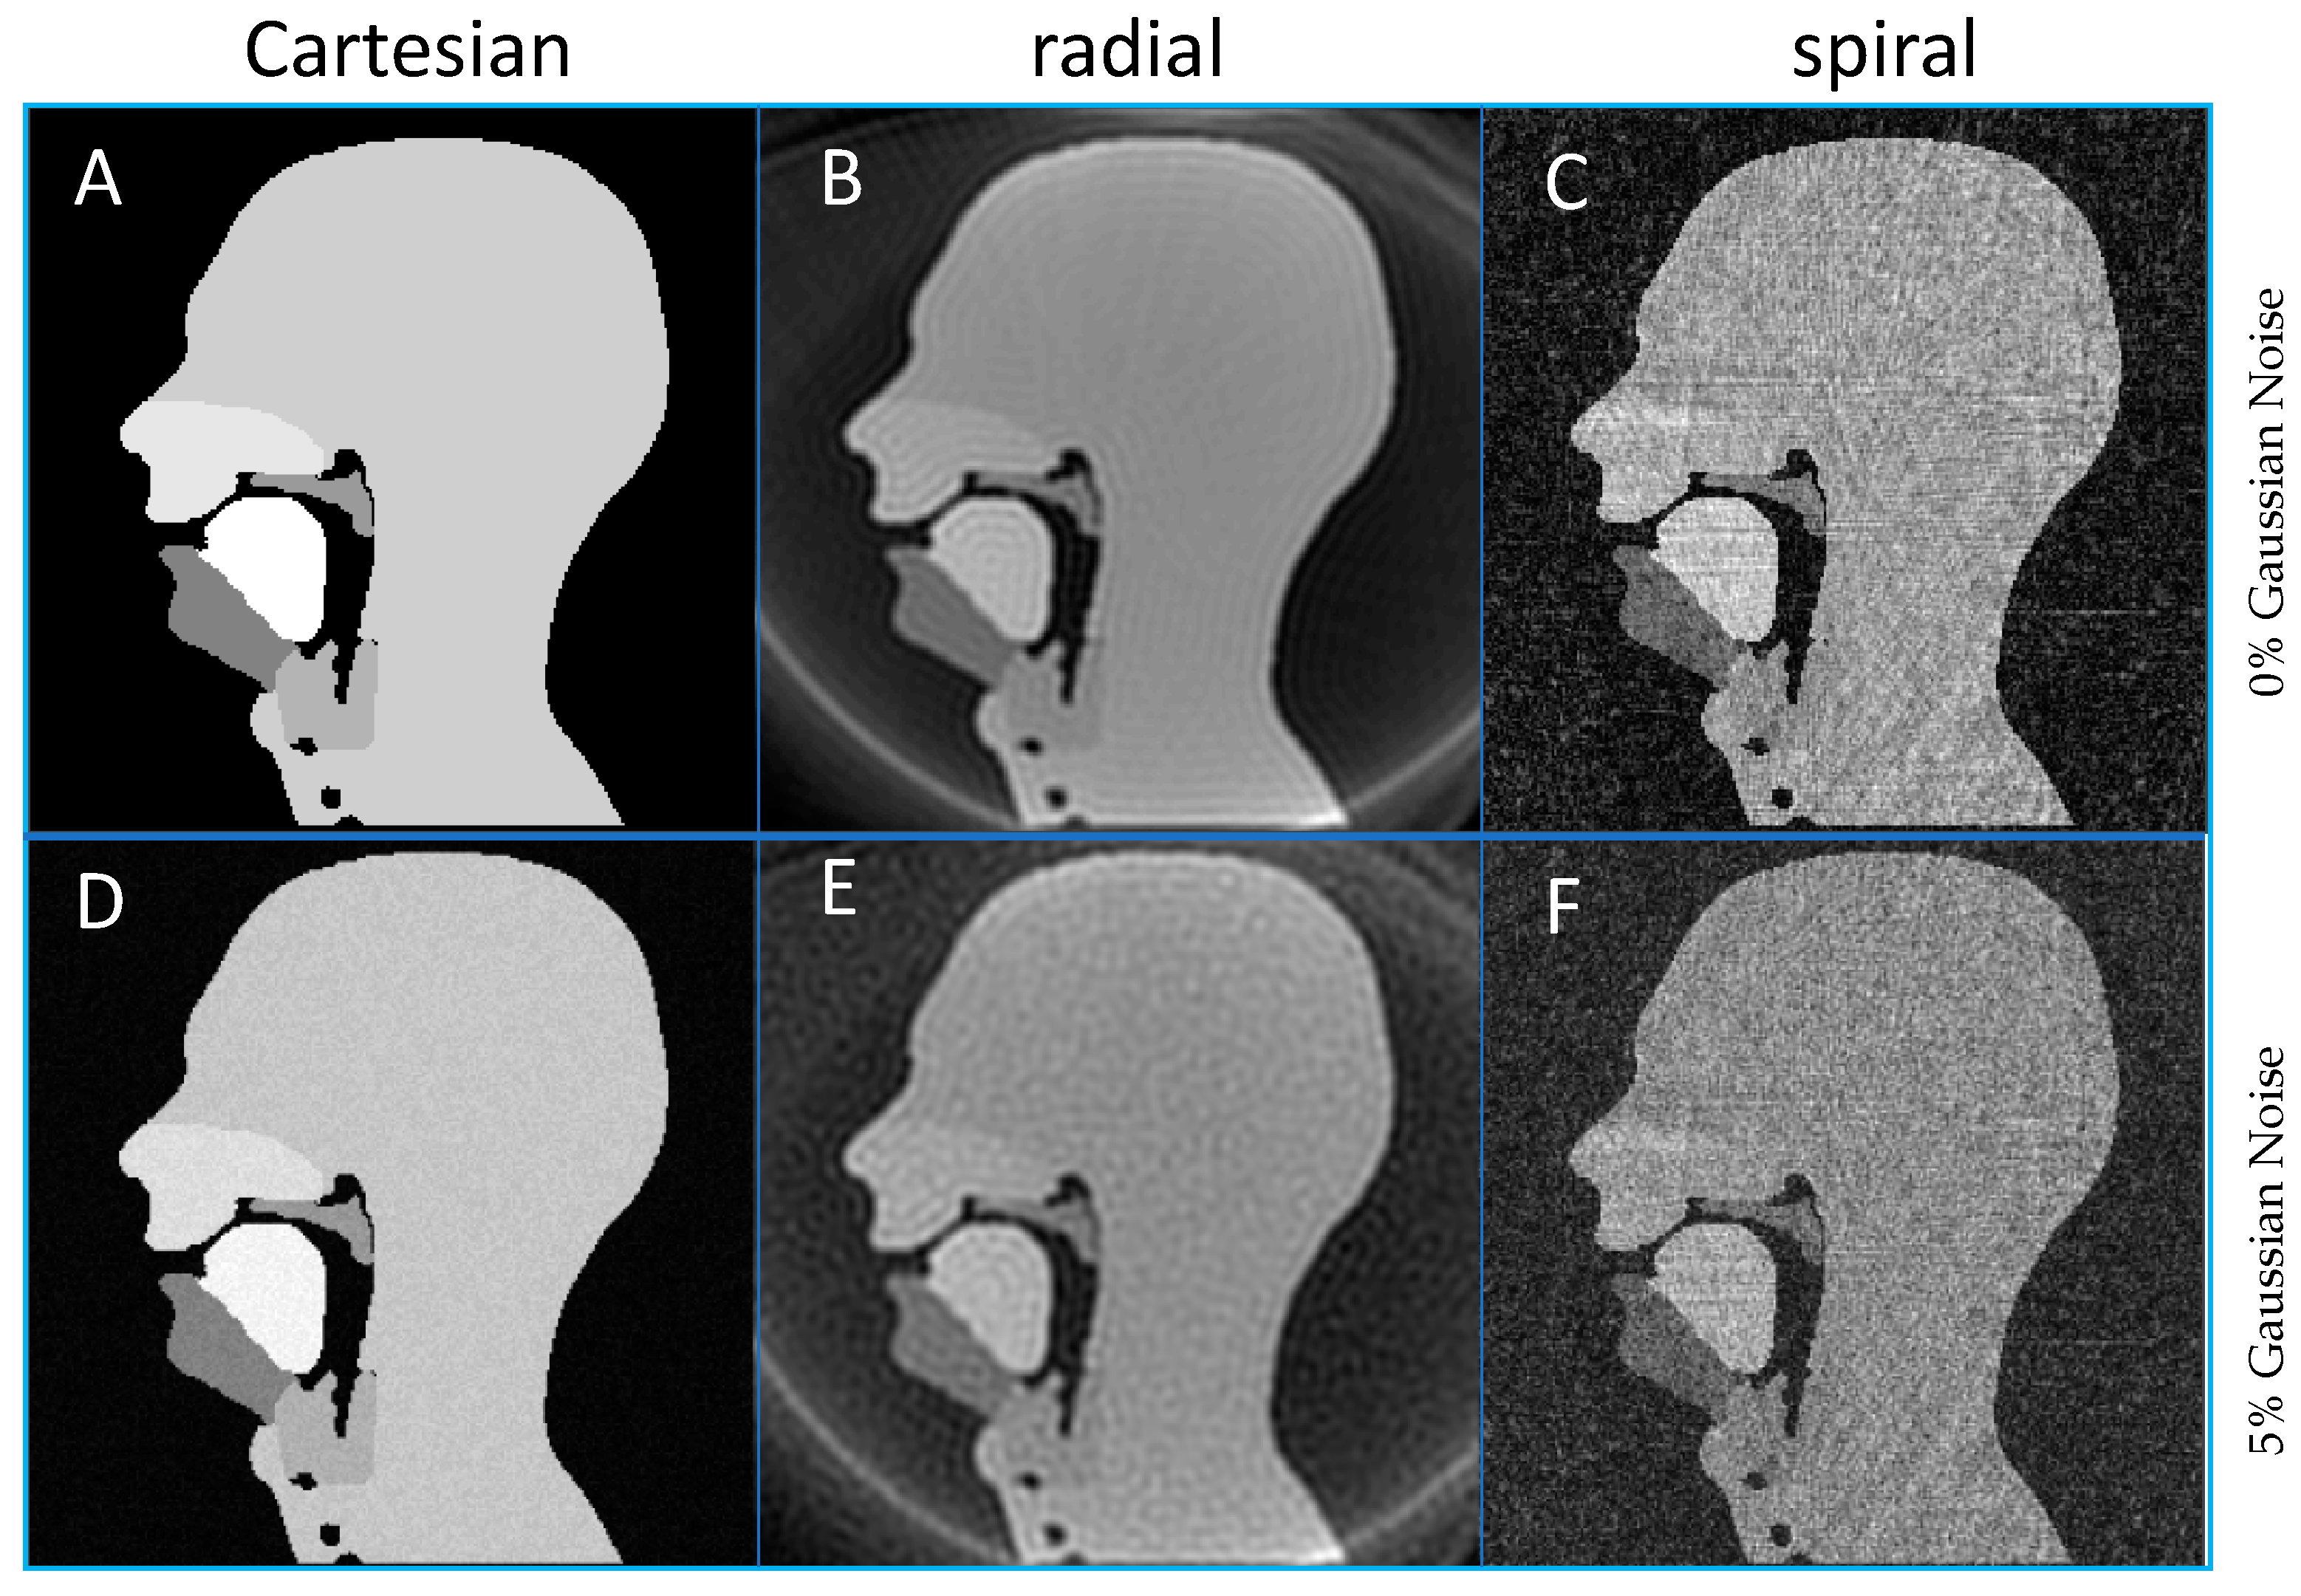

3.2. Cartesian, Radial and Spiral Trajectories

An example of reconstructed images for Cartesian, spiral and radial trajectories can be viewed in Figure 9, and the full movies of the three k-space trajectories without noise can be found in the Supplementary Materials, Videos S1 to S3. Both spiral and radial sampling trajectories allowed the individual speech organs to be viewed, which is the basic functional task required of these images in clinical speech MRI. The radial images showed the intrinsic ring aliasing artefact associated to it, as well as Gibbs artefacts near the edges of each of the speech organs, the latter of which has been reported in clinical radial imaging and is caused by the re-gridding process [103]. In the spiral images, a very streaked background noise was apparent across both of the images and this is again reported in clinical imaging as an effect of re-gridding [103] and, in this case, is an effect of multiple uncorrelated aliased images. Unlike in Cartesian imaging, correlated aliased repetitions observable in non-Cartesian acquisitions can obscure the anatomy of interest; these aliasing artefacts would not affect the diagnostic efficacy of the image.

Figure 9.

Example frames for a fully sampled k-space using different trajectories and noise level. (A,D) Cartesian, (B,E) radial, (C,F) spiral acquisitions with 0% (A–C) and 5% (D–F) noise added prior to Fourier transformation.

In quantitative terms, the RMSE was greater for radial than spiral (22.1% to 18.6%) without added noise. However, the noise had little effect on the radial images RMSE, 22.6% corresponding to a 2.26% increase, whereas it led to a 32.80% greater RMSE for the spiral trajectory (24.7%). However, the identification of the speech organs is not impaired; in particular, the velum is clearly visible throughout all simulated images and all velopharyngeal closures (when the velum touches the back of the throat) are still clearly identifiable. Consequently, despite the noise and artefacts, these images are of equivalent diagnostic quality as the original Cartesian images.